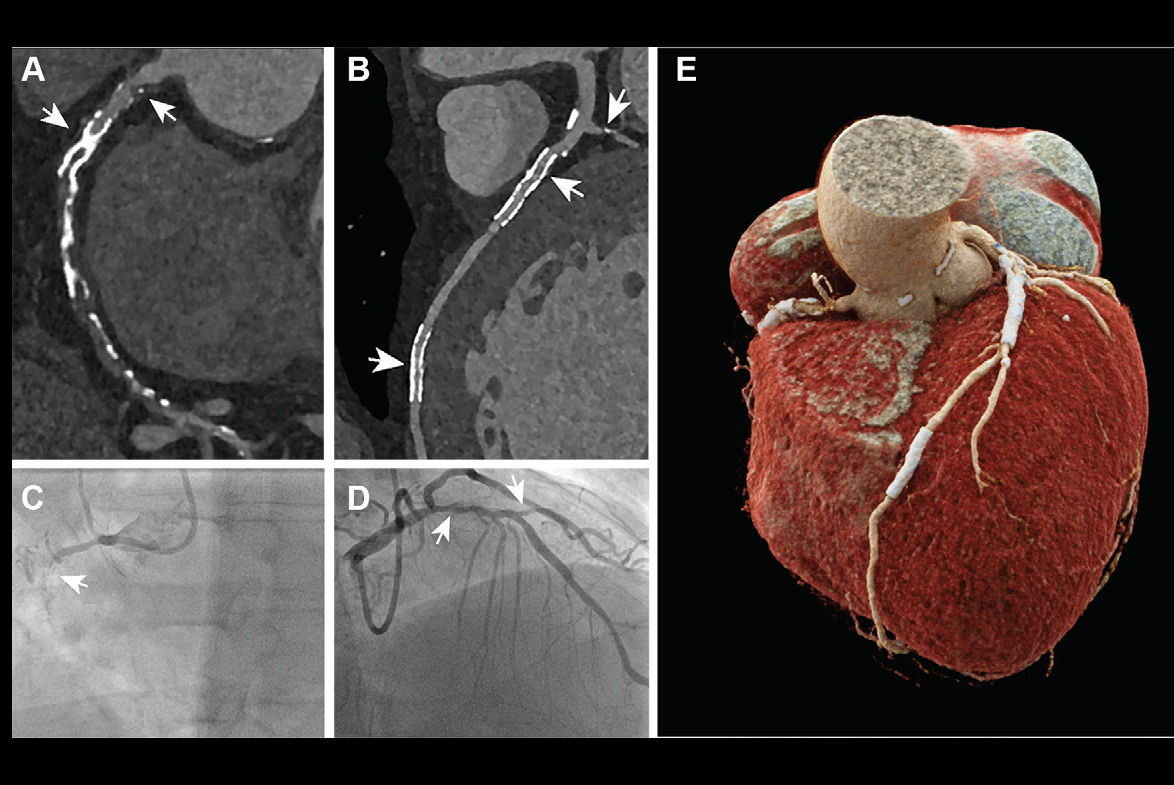

PULSE was an open-label, blinded-endpoint, randomized trial conducted at 15 sites in Europe and South America in which the participants were consecutive patients with critical stenosis who underwent percutaneous coronary intervention (PCI) for left main coronary artery disease. A total of 606 participants were randomized to either CCT-guided follow-up at six months (experimental arm) or standard symptom- and ischemia-guided management (control arm). The participants were then followed for an additional 12 months, for a total follow-up period of 18 months.